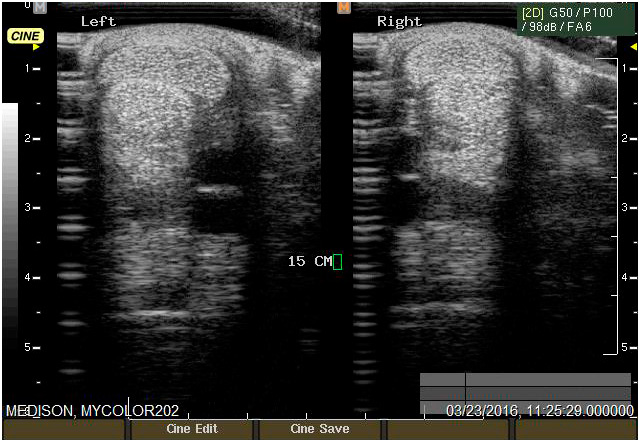

Ecografía

Cuenta con Ecografía digital de alta complejidad.

17 años de experiencia siendo una de las ecografistas más reconocidas en la práctica de equinos. Realiza pasantías en la universidad de Davis California y en Mid-Atlantic Equine Medical Center en New Jersey.